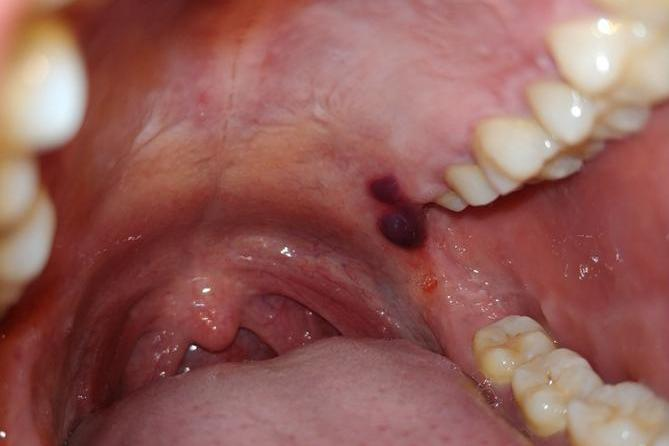

导致口腔里突然起了一个黑紫色血疱的原因多种多样,主要涉及外伤、黏膜病变及全身性疾病等多方面的因素,需根据不同原因进行针对性的治疗,如药物治疗。

- 进食过程中,不慎咬伤口腔黏膜或食用过烫食物导致烫伤,均可能使局部血管破裂,血液渗出并积聚于黏膜下,形成黑紫色的血疱。此类情况多伴有局部疼痛或不适感,但一般可自行吸收愈合。

- 口腔黏膜色素痣:虽然较为罕见,但口腔黏膜上偶可发生色素痣,表现为黑紫色斑块或血疱样改变。此类病变多为良性,但需注意其恶变风险,建议及时就医明确诊断。